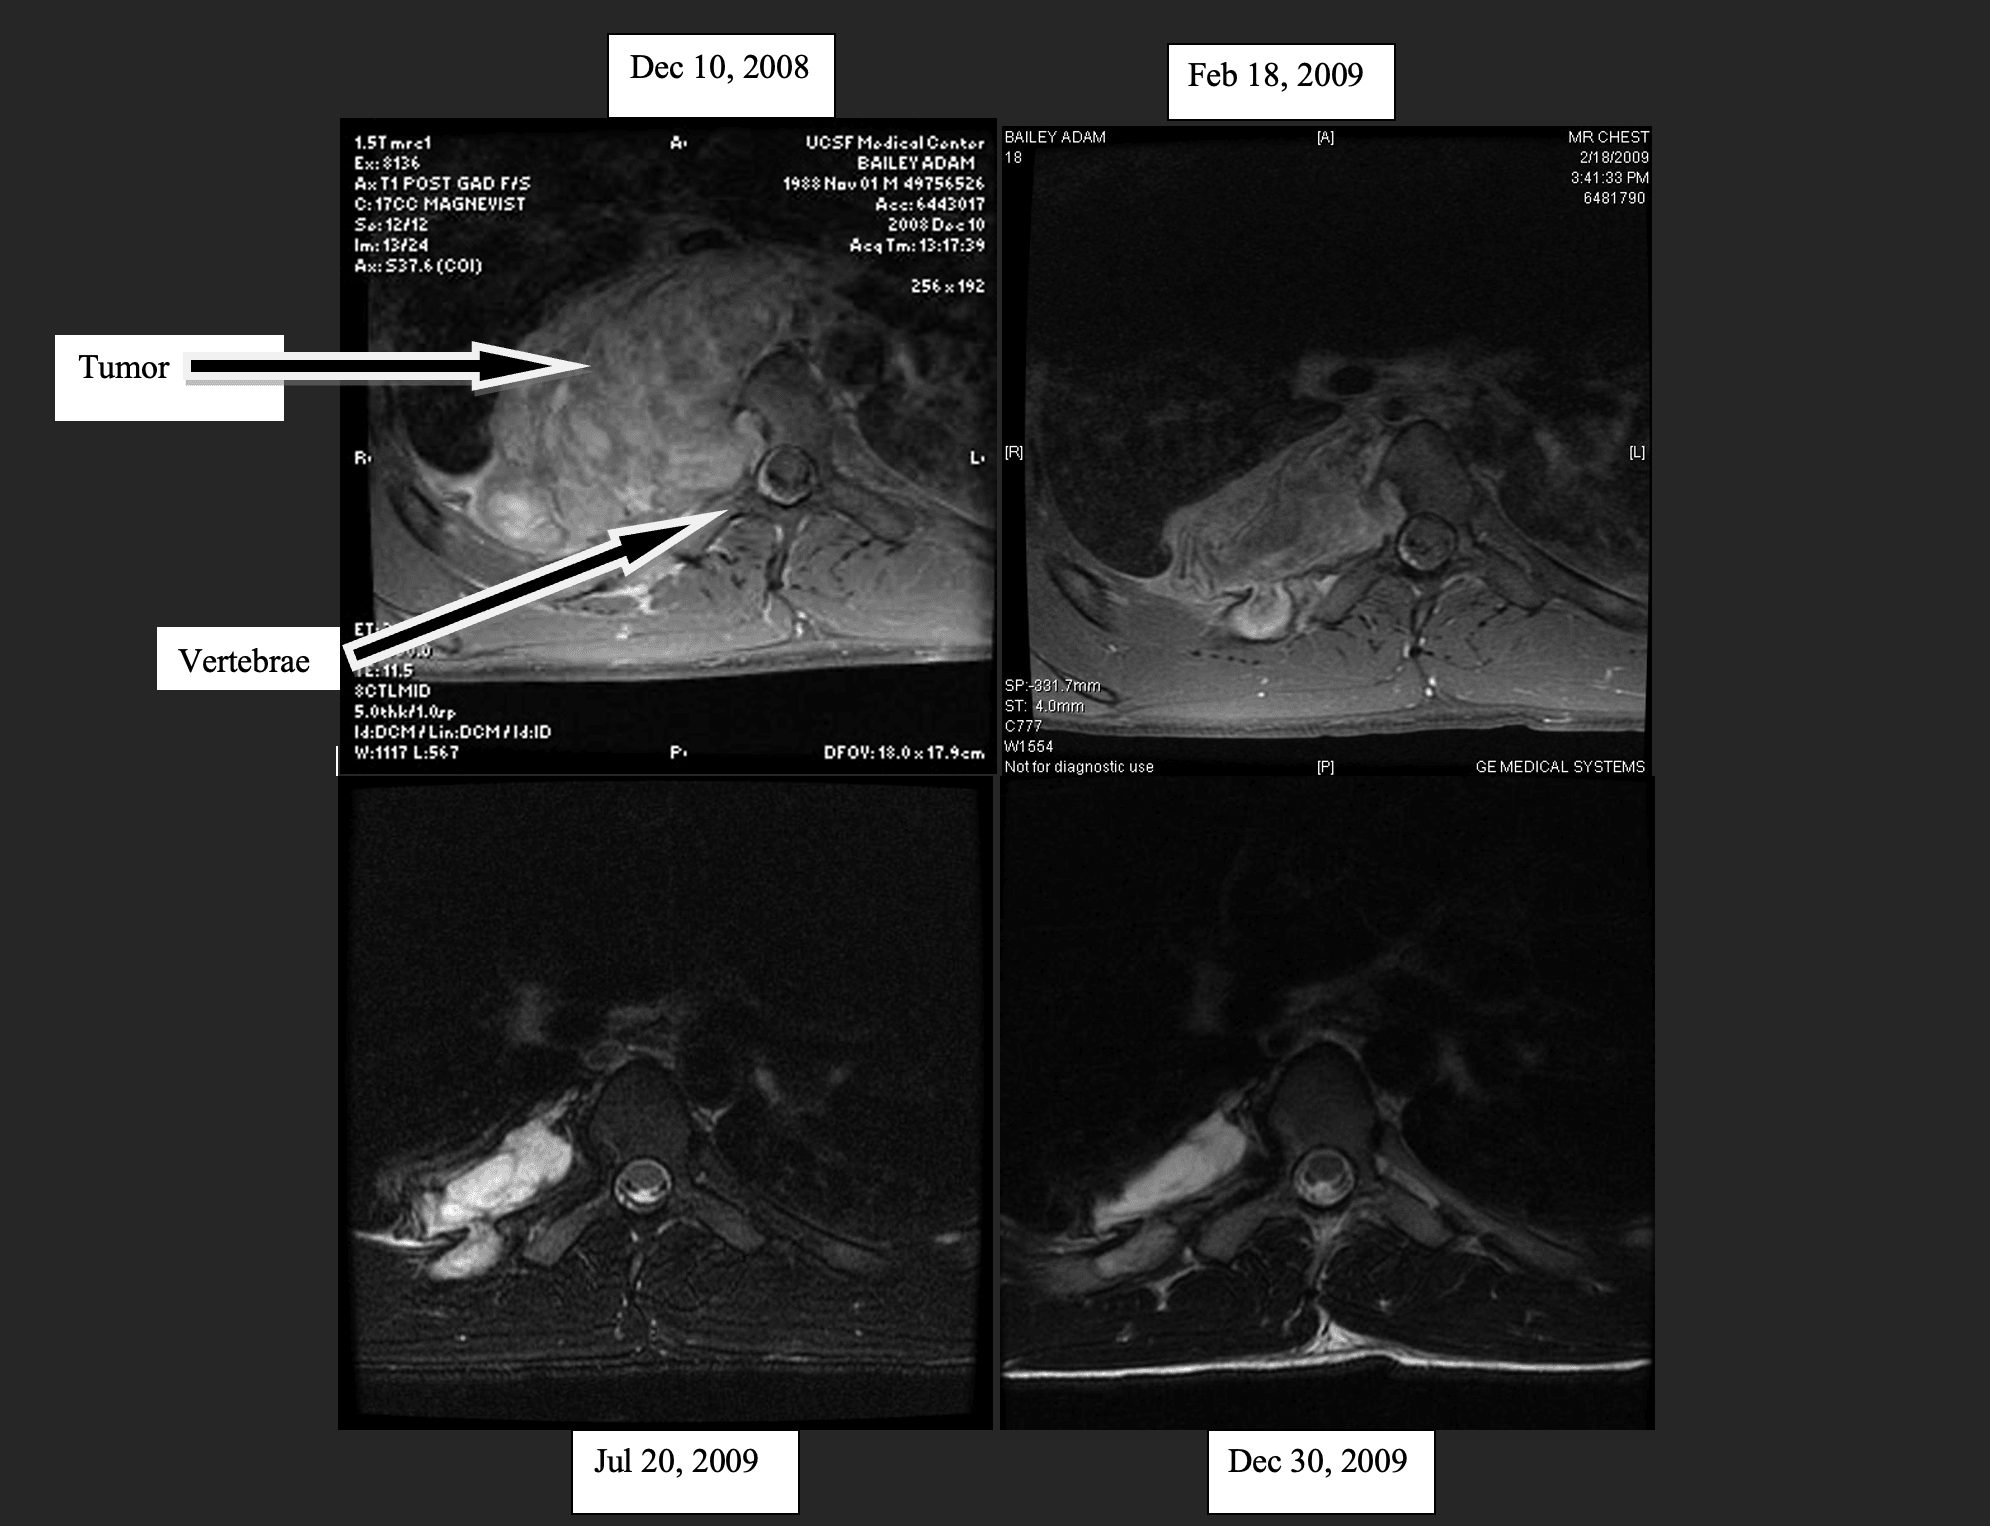

And yet I still didn’t want the path in front of me. But then, something wildly unexpected happened. Out of nowhere as I sought God and prepared for the treatment, I began to meet people who had dealt with cancer via alternative means, diet-based approaches and the like. I was skeptical yet let myself begin to research the options. Eventually, my mom and I designed a protocol from our research we thought might help. My neurosurgeon was also skeptical but agreed to give it a shot. The diet was a combination of something called the Budwig diet, alongside heavy vegetable juicing and some other supplements. We scanned 45 days later, and low and behold, half the tumor had melted away. I was stunned. My neurosurgeon was stunned, and he advised me to continue my course without his treatment. I continued the diet that year and saw a 90% reduction in its mass. The below picture is 4 successive MRI images of the tumor shrinking that first year. To this day, about 16 years later, it remains a small sliver and basically non-responsive. I consider myself healed, and my diet has been able to somewhat relax.